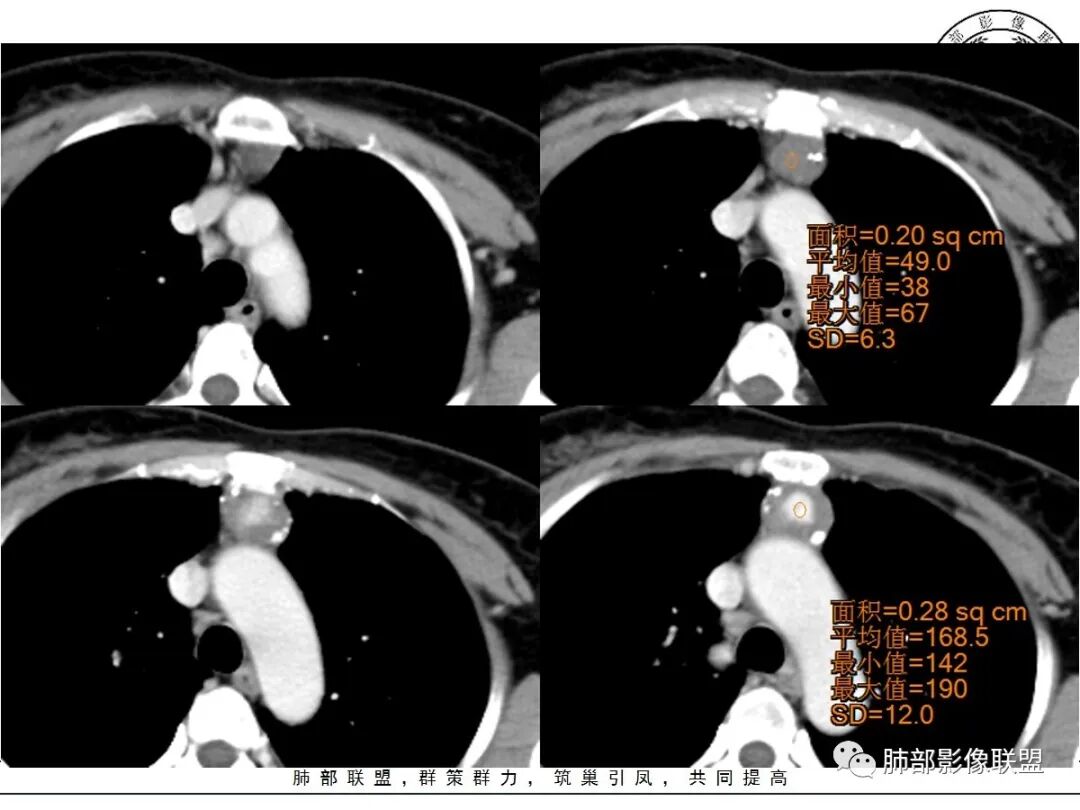

红星:女性病人48岁,前上纵隔,类圆形的实性病变,平扫密度比较均匀,周围卷见点状的钙化灶,增强扫描明显的强化, 多时相扫描中心可见跟大血管强化幅度一致的结节灶。常规胸腺瘤?鉴别血管瘤?

周太狼:中年女性,前纵隔肿块,边界清,内不规则钙化灶,增强中央明显强化,与邻近血管强化程度相似。纵隔内无明显增大淋巴结。考虑良性或低度恶性病变。疾病谱:CD、副节、血管瘤、胸腺瘤/癌。个人倾向于CD或血管瘤可能大一些。

三个石头:前纵隔占位,残余胸腺组织可见,边缘钙化,增强中央出现与血管同步强化结节,病灶延迟强化。脉管瘤?胸腺瘤?血管瘤?异位甲状腺?

中央结节状强化, 类似于血管强化

定性:偏良性病变,血管瘤?胸腺瘤?

前纵隔海绵状血管瘤的影像学特征包括:①发生于前纵隔的圆形、类圆形、不规则肿块影,边界清晰,与邻近结构分界清晰;②CT上呈稍低密度影,内见小结节状、小片状、针尖状的钙化灶,钙化灶、静脉石影是海绵状血管瘤的特征性表现。③增强后大多数肿块可显示肿块的范围及供血情况,动脉期病灶边缘呈点片状强化,静脉期及延迟期逐步向内填充,呈渐进性强化等典型特征,部分不强化或轻度强化,部分增强 后片状强化,强化程度与邻近血管相仿;血管瘤强化方式与肿块内组织成分、血窦内血栓、血流等因素有关;Moran等研究表明,肿块强化不均匀或呈轻度强化的原因可能与扩张的血窦腔内组织平滑肌增殖及炎性纤维化有关;肿块血管样强化可提示海绵状血管瘤。前纵隔海绵状血管瘤需与畸胎瘤、胸腺瘤、胸内甲腺肿、神经内分泌肿瘤等进行鉴 别 断:①畸胎瘤多呈混杂密度影,内有脂肪、毛发、钙化灶及水样密度;②胸腺瘤呈结节状、团块状影,密度较均匀,增强后强化较均匀,与周围组织分界清晰;③胸内甲状腺肿位于前上纵隔,平扫密度常较高,可见其上端与颈部甲状腺相连;④神经内分泌肿瘤多伴坏死囊变,点片状钙化,形态常呈分叶状或 不规则形,增强后肿瘤实性部分强化显著。